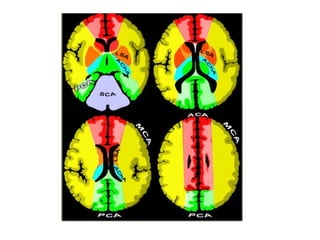

b) Cerebral Arterial Territory :

1-Posterior Inferior Cerebellar Artery

2-Superior Cerebellar Artery

3-Branches from vertebral and basilar artery

4-Anterior Choroidal artery

5-Lenticulostriate arteries

6-Anterior cerebral artery

7-Middle cerebral artery

8-Posterior cerebral artery

1-Posterior Inferior Cerebellar Artery (PICA in blue)